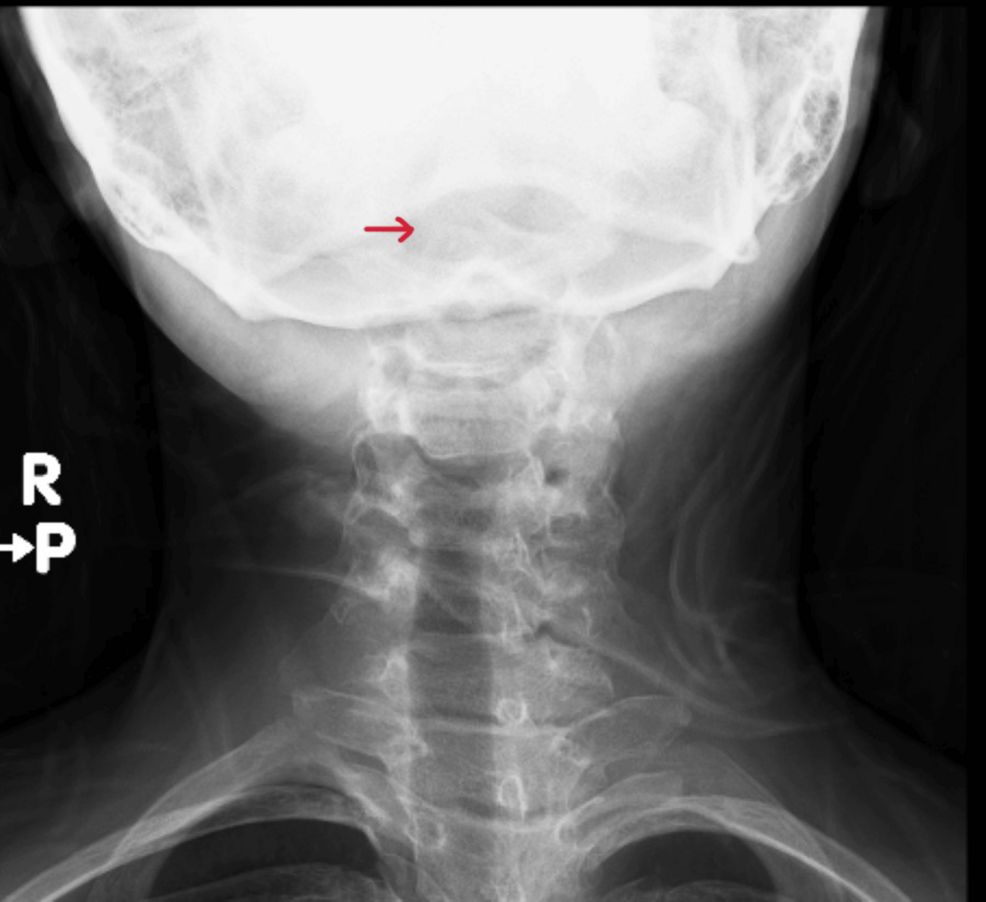

Diagnostic Evaluation: Confirming the Diagnosis

A thorough diagnostic workup is essential. Our protocol included:

* Neurological Examination: Detailed assessment of motor strength, reflexes, sensation, and coordination.

* Radiography:

* Flexion and Extension Lateral radiographs of the Cervical Spine: These are the initial imaging modality to assess for instability. Look for widening of the prevertebral space (greater than 4.5mm in children) or translation of C1 on C2.

* CT Scan: Provides more detailed bony anatomy and can identify subtle fractures or ligamentous injuries.

* MRI: The gold standard for evaluating soft tissues, including ligaments, spinal cord, and nerve roots. MRI can detect spinal cord compression and edema. MRI atlantoaxial subluxation is key for accurate assessment.